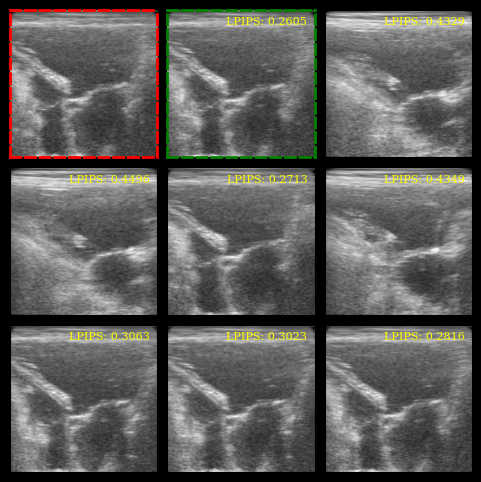

We plot the images, highlight the reference (red border) and the most similar image (green border), and display the LPIPS scores.

[9]:

batch_np = ops.convert_to_numpy(batch)

batch_np = ((batch_np + 1) / 2 * 255).astype(np.uint8)

fig, _ = plot_image_grid(batch_np, remove_axis=False)

axes = fig.axes[:n_imgs]

# Red border for reference image

for spine in axes[0].spines.values():

spine.set_edgecolor("red")

spine.set_linewidth(2)

spine.set_linestyle("--")

# Green border for most similar image

most_similar_idx = lpips_scores.argmin()

for spine in axes[most_similar_idx + 1].spines.values():

spine.set_edgecolor("green")

# LPIPS scores as text

for ax, lpips_score in zip(axes[1:], lpips_scores):

ax.text(

0.95,

f"LPIPS: {float(lpips_score):.4f}",

ha="right",

va="top",

transform=ax.transAxes,

fontsize=8,

color="yellow",

)

plt.show()